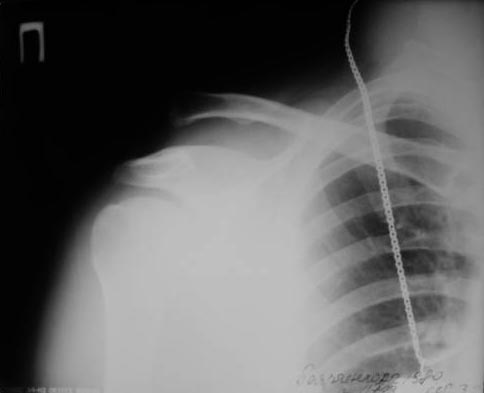

[Ortho] фиксация КАС по Веберу

А зачем фиксировать по Веберу, если можно двумя винтами чрезкожно.

В начале использовали канюлированные, а затем обычные (канюлированные

жалко). Фото в приложении. Операция под ЭОПом.

Травма свежая.